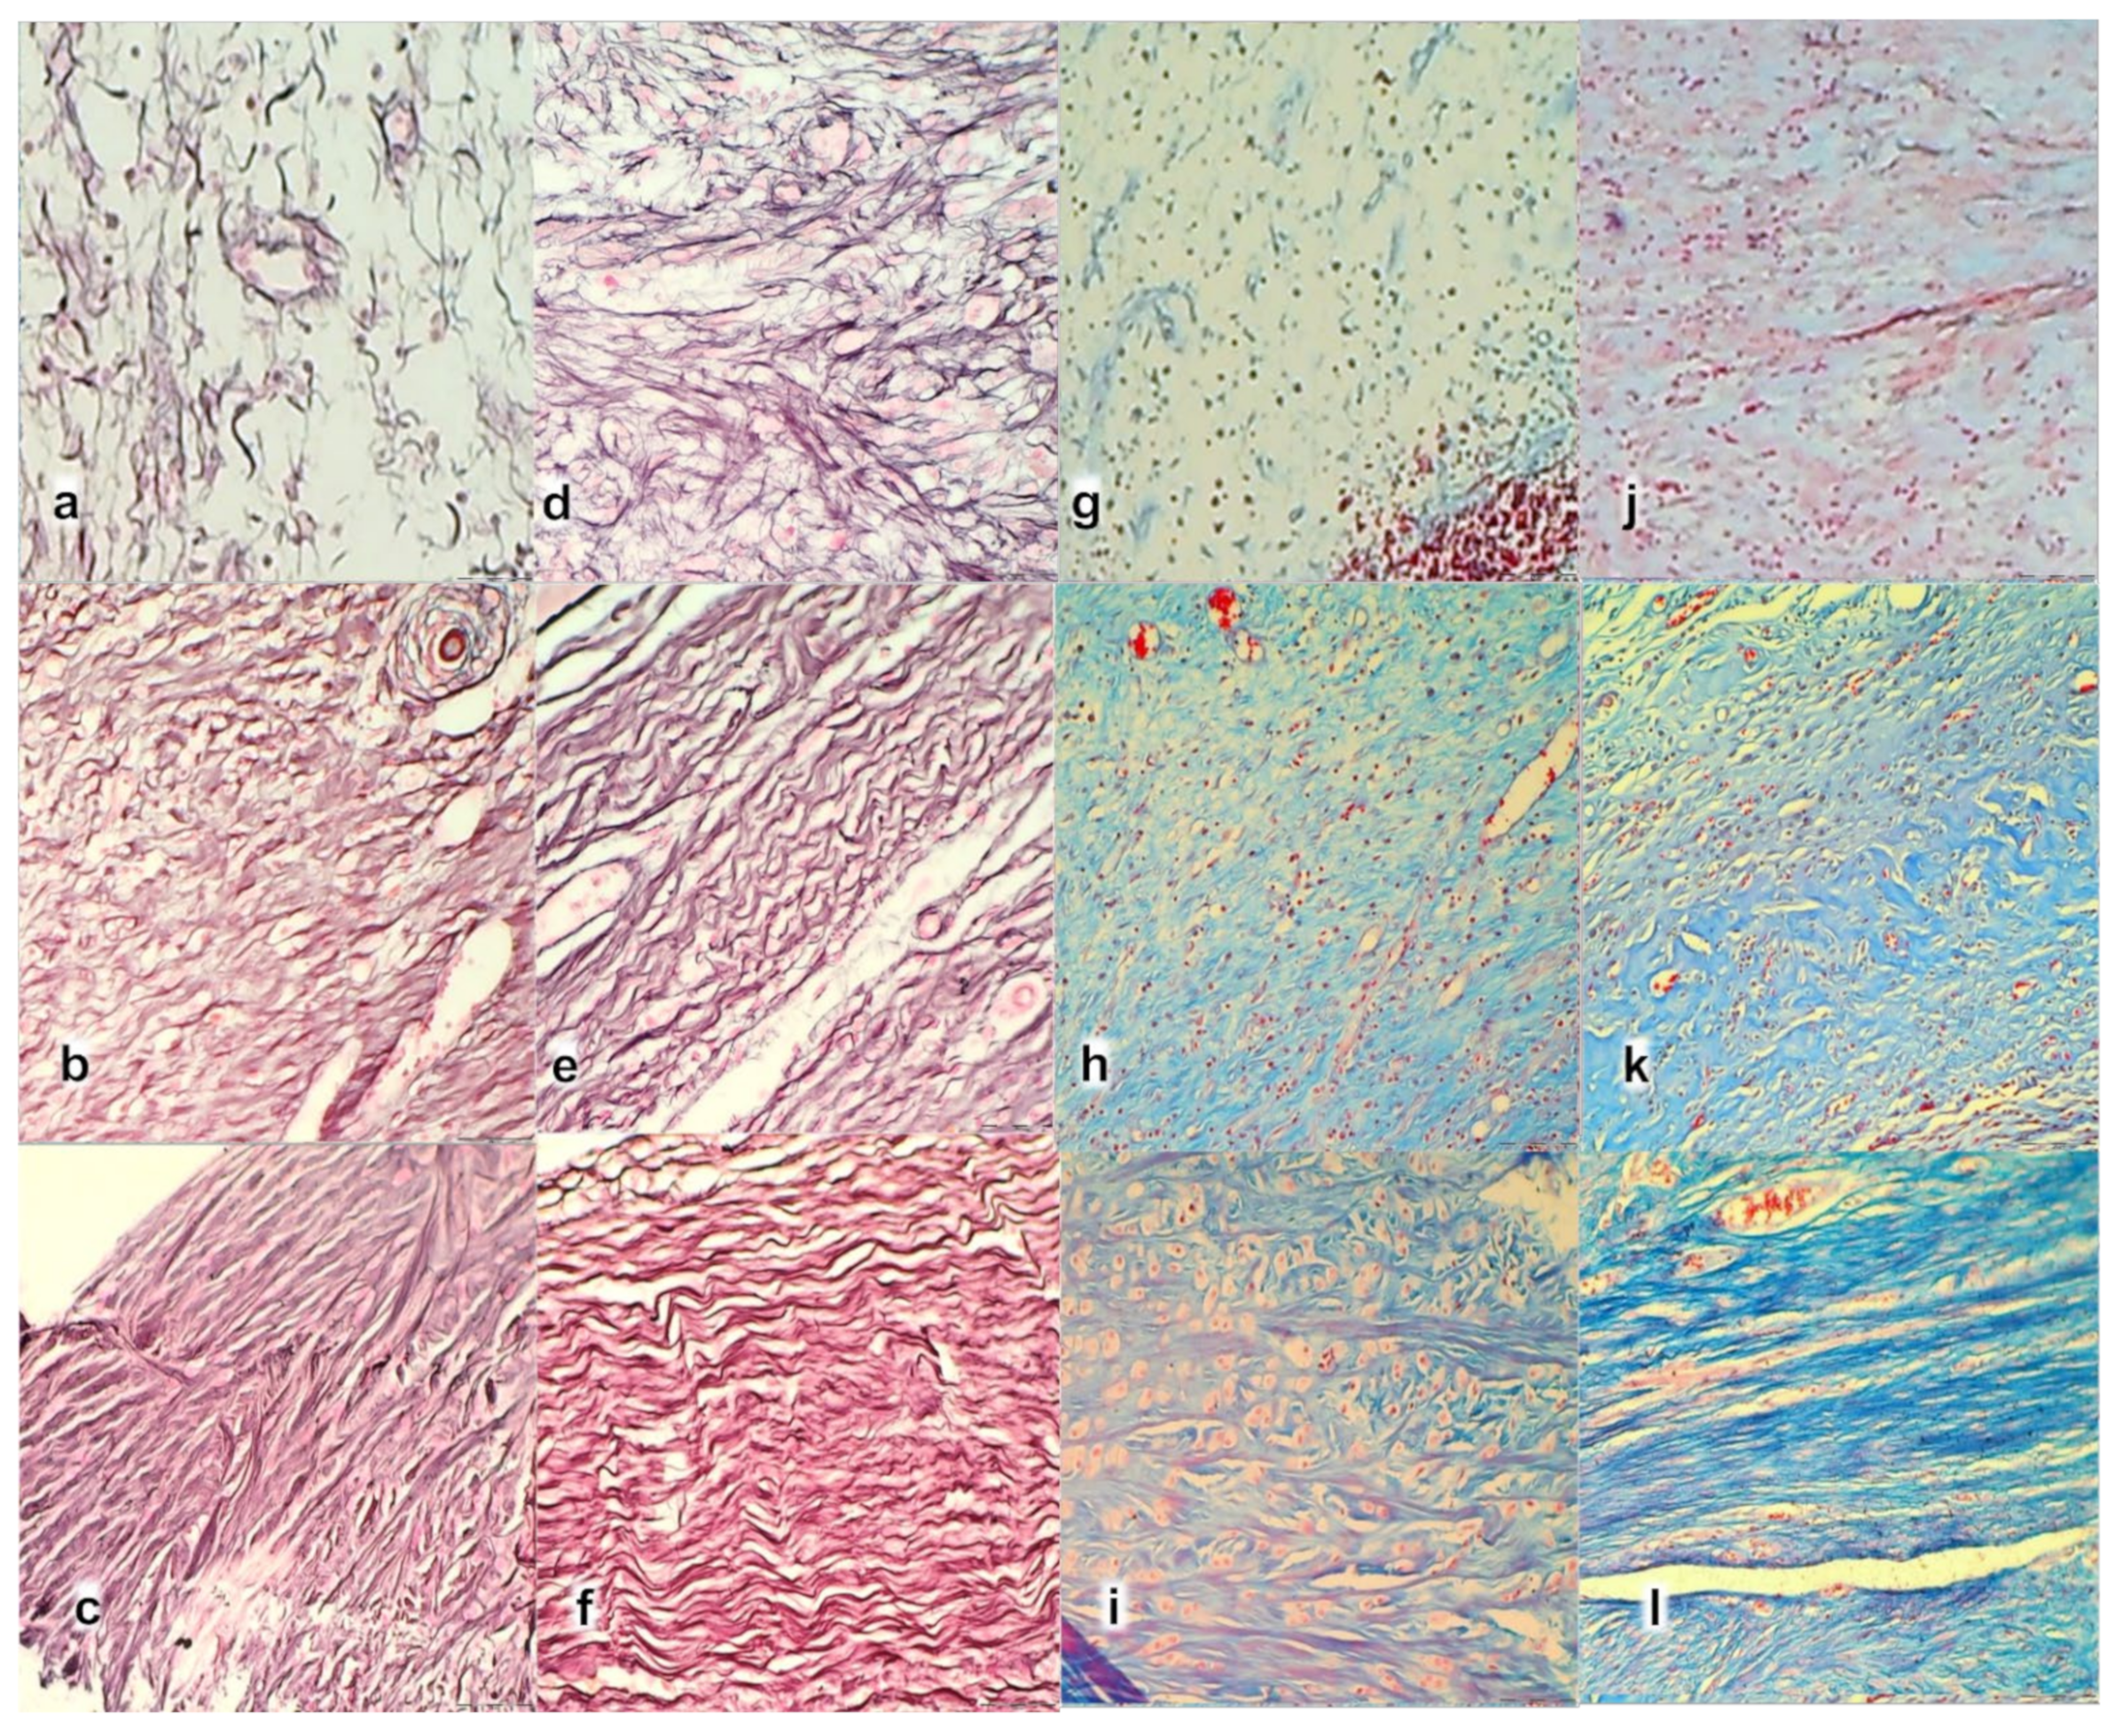

2.7. Microscopy